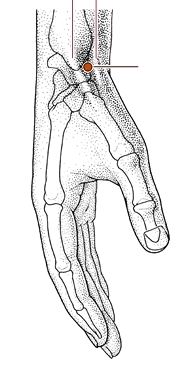

阳溪

经穴名。出《灵枢•本输》。别名中魁。属手阳明大肠经。经(火)穴。在腕背横纹桡侧,手拇指向上翘起时,当拇短伸肌腱与拇长伸肌腱之间的凹陷中。布有桡神经浅支,头静脉、桡动脉本干及其腕背支。主治头痛,目赤肿痛,齿痛,咽喉肿痛,耳聋,手腕痛等。